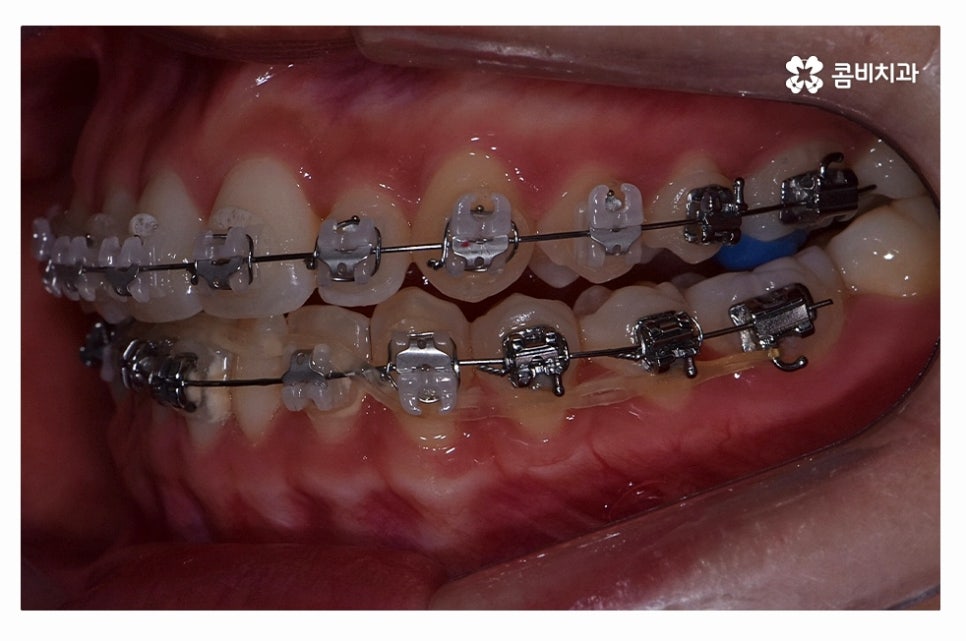

오늘 보여드릴 사례도 덧니교정이 비발치로 진행이 된 사례이며

치아의 이동 공간과 치아 상태, 골격, 얼굴형 등을

종합적으로 판단할 때 비발치로도 진행이 가능했던 사례라고 할 수 있어요.

교정 장치의 선택에 있어서는 다양한 교정 장치의 선택이 가능한데

심미성이 강조된 설측교정부터 콤비교정,

위 환자분의 사례처럼 클리피씨교정이 보편적으로 많이 활용되고 있는데요.

클리피씨교정은 치아의 이동이 일반 장치에 비해 상대적으로

빠르기 때문에 치료 기간이 단축될 수 있으며

통증의 감소, 내원 횟수를 줄일 수 있다는 장점 등이 있어요.